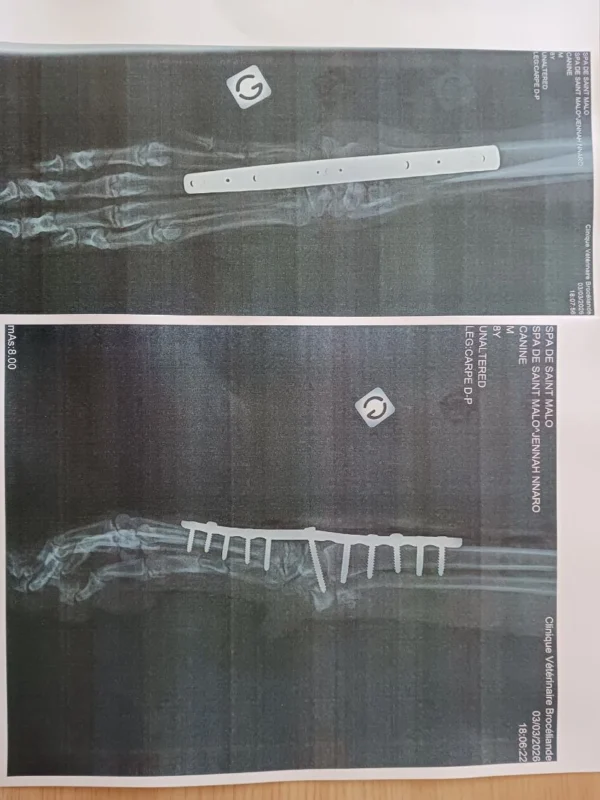

Vous trouverez ci-contre les radios de JENNAH NNARO , vous comprendrez mieux pourquoi il sera peut-être obligatoire de lui enlever toutes ces plaques et toutes ces vis.

Dernière chose, contrairement à ce que j’ai laissé entendre, le Dr Desbuquois n’a bloqué l’articulation que sur une seule patte, je suppose que c’est celle qui le fait le plus boiter.